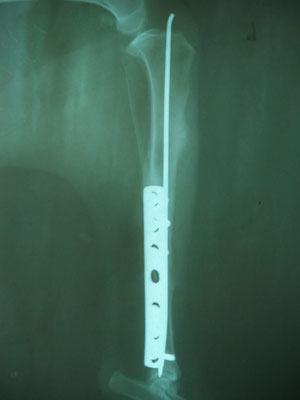

Κάταγμα στο κάτω τρίτο της διάφυσης της αριστερής κνήμης και τοποθέτηση στην έσω επιφάνεια μεταλλικής πλάκας με 3 κοχλίες στο άνω τμήμα και 3 κοχλίες στο κάτω.Επίσης τοποθετήθηκε ενδομυελικός ήλος.

Στις 16/06/2010 αφαιρέθηκαν η μεταλλική πλάκα με τους 6 κοχλίες ενώ ο ενδομυελικός ήλος παρέμεινε.Το ζώο καλύφθηκε αντιβιοτικά με 2,5 ml κεφαλοσπορίνη, 1,5 ml gentamycin, 1ml dalacin και 2ml marbocyl